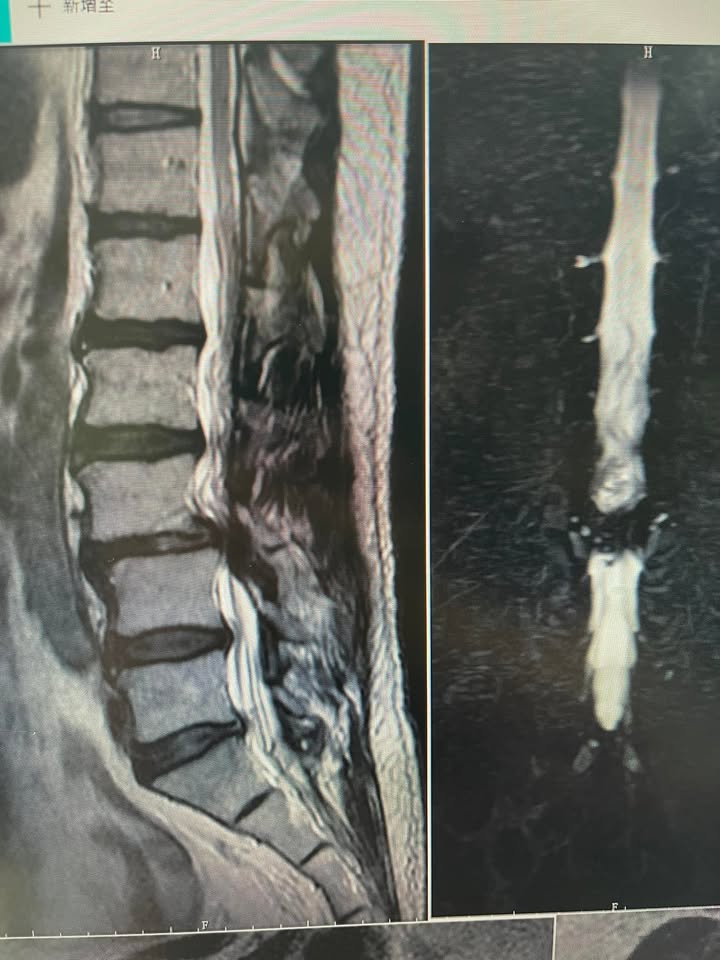

🔵腰椎嚴重滑脫合併狹窄免開大刀。